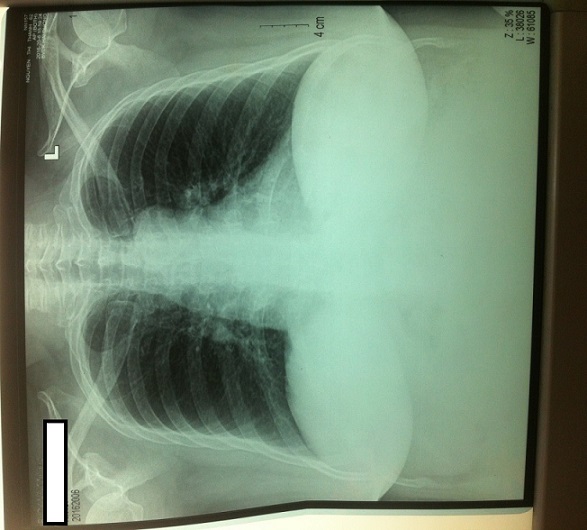

7. Chụp x quang xương bàn chân và lồng ngực: không thấy tổn thương.